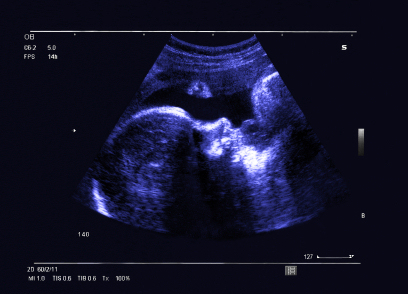

According to the results, 88 unique lesions were identified and the mean lesion diameter was 6.7-mm. Eight lesions were palpable. Of the 968 possible detections, 535 or 55% were made by the readers. As a group, the detection rate ranged from 49% to 66% with 36% of lesions seen by only two to three investigators.

"We looked at what features contributed to lesion detection. Dimension and size were dominant characteristics that played into this with very small lesions, under 3 mm, being very difficult to detect," Berg said.

She offered an example of a 4-mm lesion that was small and deep within the breast. It was seen by 63% of the readers. However, these readers were divided on whether the lesion was a complicated cyst with a BI-RADS 3 or a simple cyst with BI-RADS 2.

Larger lesions were more consistently detected with the readers' detection rate coming in at 97% for lesions 11 mm or larger and 86% for lesions 9.1 mm to 11 mm. The detection rate ranged from 18% to 67.6% for lesions ranging from 3 mm to 9 mm.